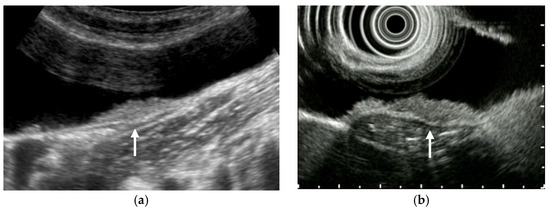

Figure 13. Discontinuity of an outer hyperechoic layer. A high-frequency transducer showed the discontinuity of an outer hyperechoic layer (arrow) in focal GWT (a), EUS also delineated the thinning of an outer hyperechoic layer (arrow) (b) (GBC case).

Typical US findings in wall thickening GBC include hypoechoic, irregular wall thickening due to tumor invasion. According to a study using HRUS, loss of the multiple layer pattern was detected in 64.3% of wall-thickening-type GBC [9]. Furthermore, tumor invasion into the adipose layer of the subserosa causes the irregularity of the outer hyperechoic layer and tumor invasion beyond the subserosa causes the discontinuity of the outer hyperechoic layer [49] (Figure 13). On CEUS, the destruction of the GB wall intactness was absent in benign diseases, and the sensitivity, specificity, and accuracy in the differential diagnosis between malignant and benign GB diseases were 84.8%, 100%, and 93.8%, respectively [51]. According to a systematic review of CEUS, discontinuity of the GB wall in differentiating benign and malignant diseases showed the highest sensitivity (82%) and specificity (93%) among all malignant features on CEUS [50].